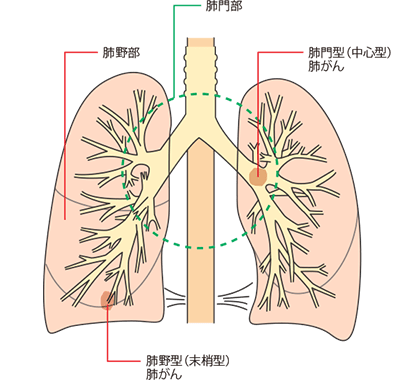

①肺がんの発生部位による違い

肺の入り口付近(肺門型肺がん):初期の段階から咳、痰や血痰などが発現します。

肺の奥(肺野型肺がん):初期に自覚症状はなく、進行して肺周囲の臓器に浸潤すると症状が現れます。

肺の中心にがんができる肺門型肺がんは、早期から咳や痰、血痰などの症状がでますが、肺の端のほうにがんができる肺野型肺がんでは初期症状はほとんどなく、進行期になって息切れや呼吸困難などがあらわれます。

肺がんはできた部位によって肺門型(肺の中心部にできたがん)、肺野型(肺の端にできたがん)に分けられ、型によって症状の出方が異なります。

肺門型の肺がんは気道に近い部位にでき、気道が刺激されるので、早期のうちから咳や喀痰、血痰があらわれることがあります。一方、肺野型の肺がんは気道から遠い部位にできるので、多くの場合、進行するまでは血痰はあらわれにくく、無症状で経過します。術後に血痰がでた場合は再発が疑われます。

肺がんのがん細胞は顕微鏡で見ることによって、4つの組織型に分類されます。組織型によって、性質やできる部位が異なります。そのほかにも、治療方法による分類や発生部位による分類があります。自分の肺がんの種類をきちんと把握して、今後の治療について主治医とよく話し合いましょう。

腺がん

唾液の出る唾液腺や胃液の出る胃腺などの腺組織とよく似た形をしているがんのことです。腺がんは、多くの場合、肺の奥のほう(肺野部)の細かく枝分かれした先にできます。女性やタバコを吸わない人にできる肺がんの多くがこの腺がんで、肺がん全体の半数程度を占めます。

扁平上皮がん

皮膚や粘膜など体の大部分をおおっている組織である扁平上皮によく似た形をしているがんのことです。扁平上皮がんはタバコとの関係がきわめて濃厚で、大部分は肺の入り口に近い肺門部にでき、肺がん全体の25〜30%を占めます。

その他、肺がんはがんの発生部位によって肺門型肺がんと肺野型肺がんに分けられます。

| 肺門型肺がん |

| 肺野型肺がん |

肺門型肺がんと肺野型肺がん